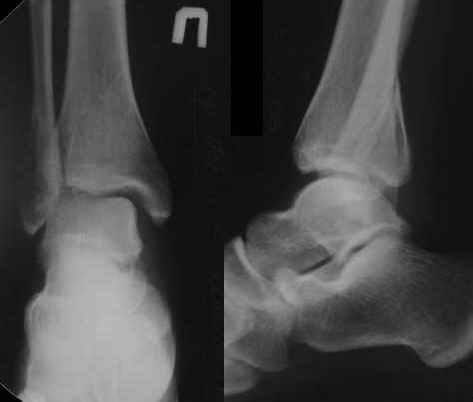

Тему неоднократно разбирали (см. архив), как всегда, недостаточны ренгенологические исследования - кроме прямого и боковых снимков, еще нужна косая ренгенограмма для определения ankle mortise, без мортиз снимка трудно определить высоту и ротацию малоберцовой. (снимки)

Ренгенология даст ответ как классифицировать перелом, на сегодня применяется классификация “Lauge Hansen fracture classification SER supination-external rotation или supination-eversion classification Danis

Weber А, В, С.”

Показания для фиксации: укорочения и ротация малоберцовой, особенно обращают внимание на любой подвывих таранной кости: неустраненый подвывих впоследствии приводит к раннему артрозу. Задний край фиксирует тогда, когда перелом составляет около 25% суставной поверхности голеностопного сочленения и смещение более 2мм.

По снимку ваш случай относится к Weber В, фиксацию производят восстановлением длины малоберцовой кости, под ренгеном (ЭП)контролем, для этого я предпочел бы латеральный доступ, остеотомия по линии перелома, удлинение малоберцовой засчет скоса линии остеотомии, компрессия “lag technique”по линии остеотомии и фиксацию провести латеральной пластиной. Отдельный задний доступ, остеотомия по линии перелома, репозиция и фиксация заднего края вашим предпочтительным методом: 3.5мм шурупом с шайбой или пластиной Antiglide Butress

method. При восстановленном суставе, уменьшится медиальная щель, а при Weber В повреждается только передне-нижняя межберцовая связка синдесмоза, повреждение которой приводит к наружной ротации

малоберцовой, но после восстановления всех смещений, связка автоматический приближается к исходному и нет необходимости восстановления синдесмоза.